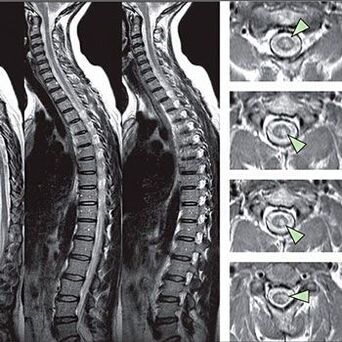

Krūškurvja mugurkaula osteohondrozes diagnosticēšanas metodes

Lai identificētu jutīguma traucējumu pazīmes, tiek veikti īpaši funkcionālie testi. Visinformatīvākā diagnozes iespēja no instrumentālajām metodēm ir X -ray veiktspēja. Tomēr, lai veiktu rūpīgu mugurkaula izpēti, bieži tiek veikti MRI un CT. Ja aizdomās par sirds un asinsvadu sistēmas slimībām, pacientam ieteicams iziet EKG procedūru.